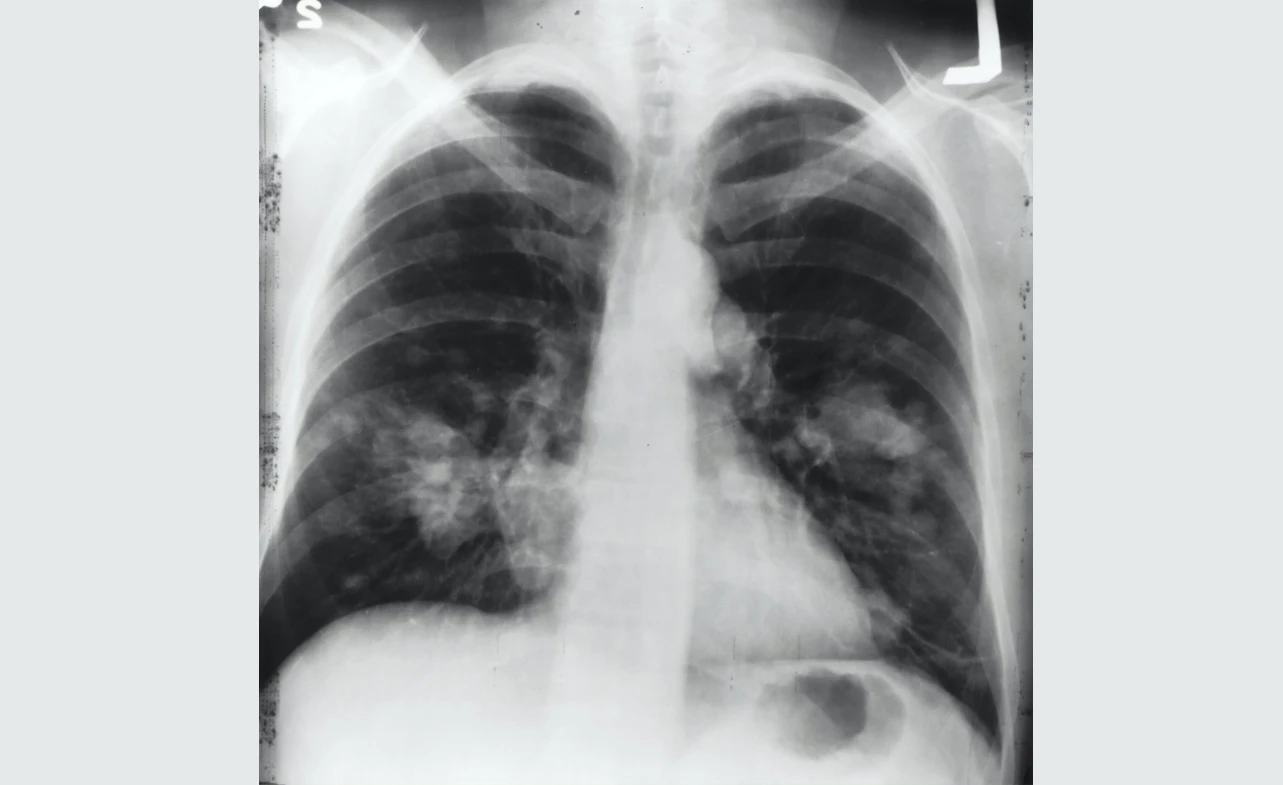

Lung cancer can spread (metastasize) from the lungs to other parts of the body, a process known as metastatic cancerStage 4 lung cancer is the most advanced stage of the disease, indicating that cancer has spread to other areas of the body. The development and spread of cancer can vary widely among individuals.

Common sites of metastasis for lung cancer include the liver, bones, brain, and adrenal glands. While treatment may help slow the progression of the disease and relieve symptoms, stage 4 lung cancer is typically not curable.

As the disease progresses, patients may experience symptoms such as shortness of breath, fatigue, loss of appetite, weight loss, and persistent coughing. It is important to work closely with your medical team to manage symptoms and ensure the best possible quality of life.